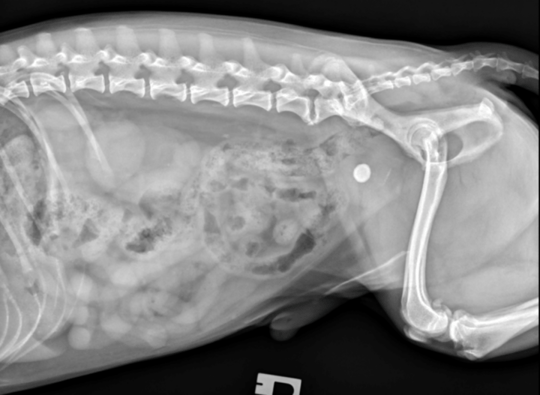

This case involved a 12-year-old neutered male Miniature Schnauzer with a six-month history of progressive lethargy and weight loss despite a good appetite, presenting with an acute onset of progressive stranguria. Physical examination revealed poor body and muscle condition; firm and irregular prostatomegaly was appreciated following digital rectal examination.

Haematology, biochemistry and urinalysis were unremarkable. Abdominal ultrasonography identified a large heterogenous prostate and marked local lymphadenopathy, raising concern of metastatic neoplasia. Fine needle aspiration was performed and was consistent with prostatic carcinoma (Figure 3). The patient was euthanised due to progressive disease and clinical signs.